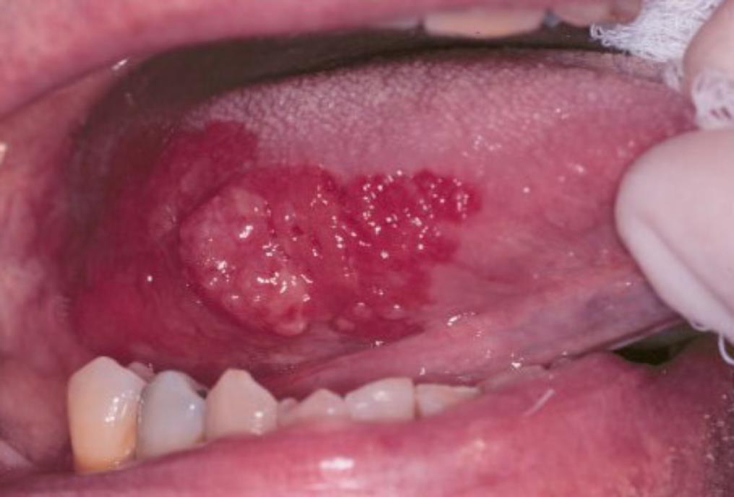

Oral squamous cell carcinoma (SCC) is a malignancy of the oral mucosal epithelium, strongly associated with tobacco, alcohol, and HPV. It frequently arises on the lower lip, floor of mouth, or lateral tongue, and may present as ulcerative or nodular lesions. Precursor lesions such as leukoplakia and erythroplakia are important warning signs. Early recognition and excision are critical, but many cases already show nodal spread at diagnosis.

- Progresses to nodular masses or necrotic ulcers

- Erythroplakia: Well-defined red, velvety plaque

- Up to 5–15% transform to invasive carcinoma